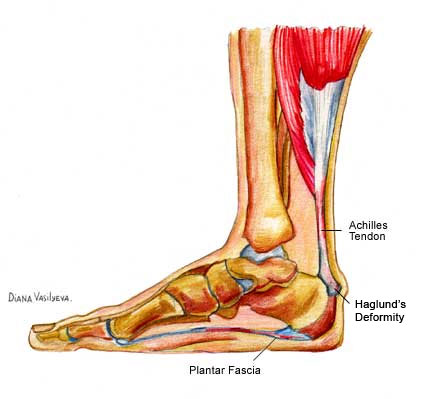

Анатомия голеностопа: Сухожилия и их строение